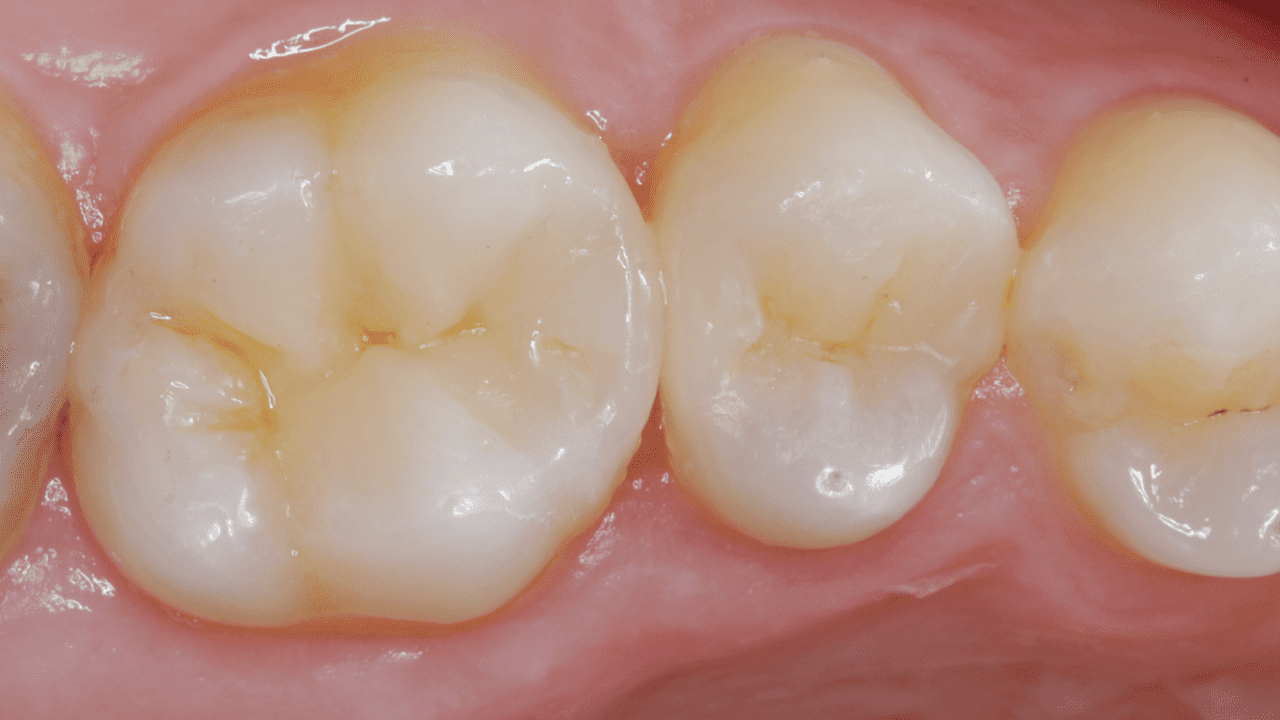

Results: Two-week recall. Final restoration and excellent gloss retention with Neo Spectra® ST universal composite A2 and BW giving the tooth back its lost anatomy and natural esthetic appearance.